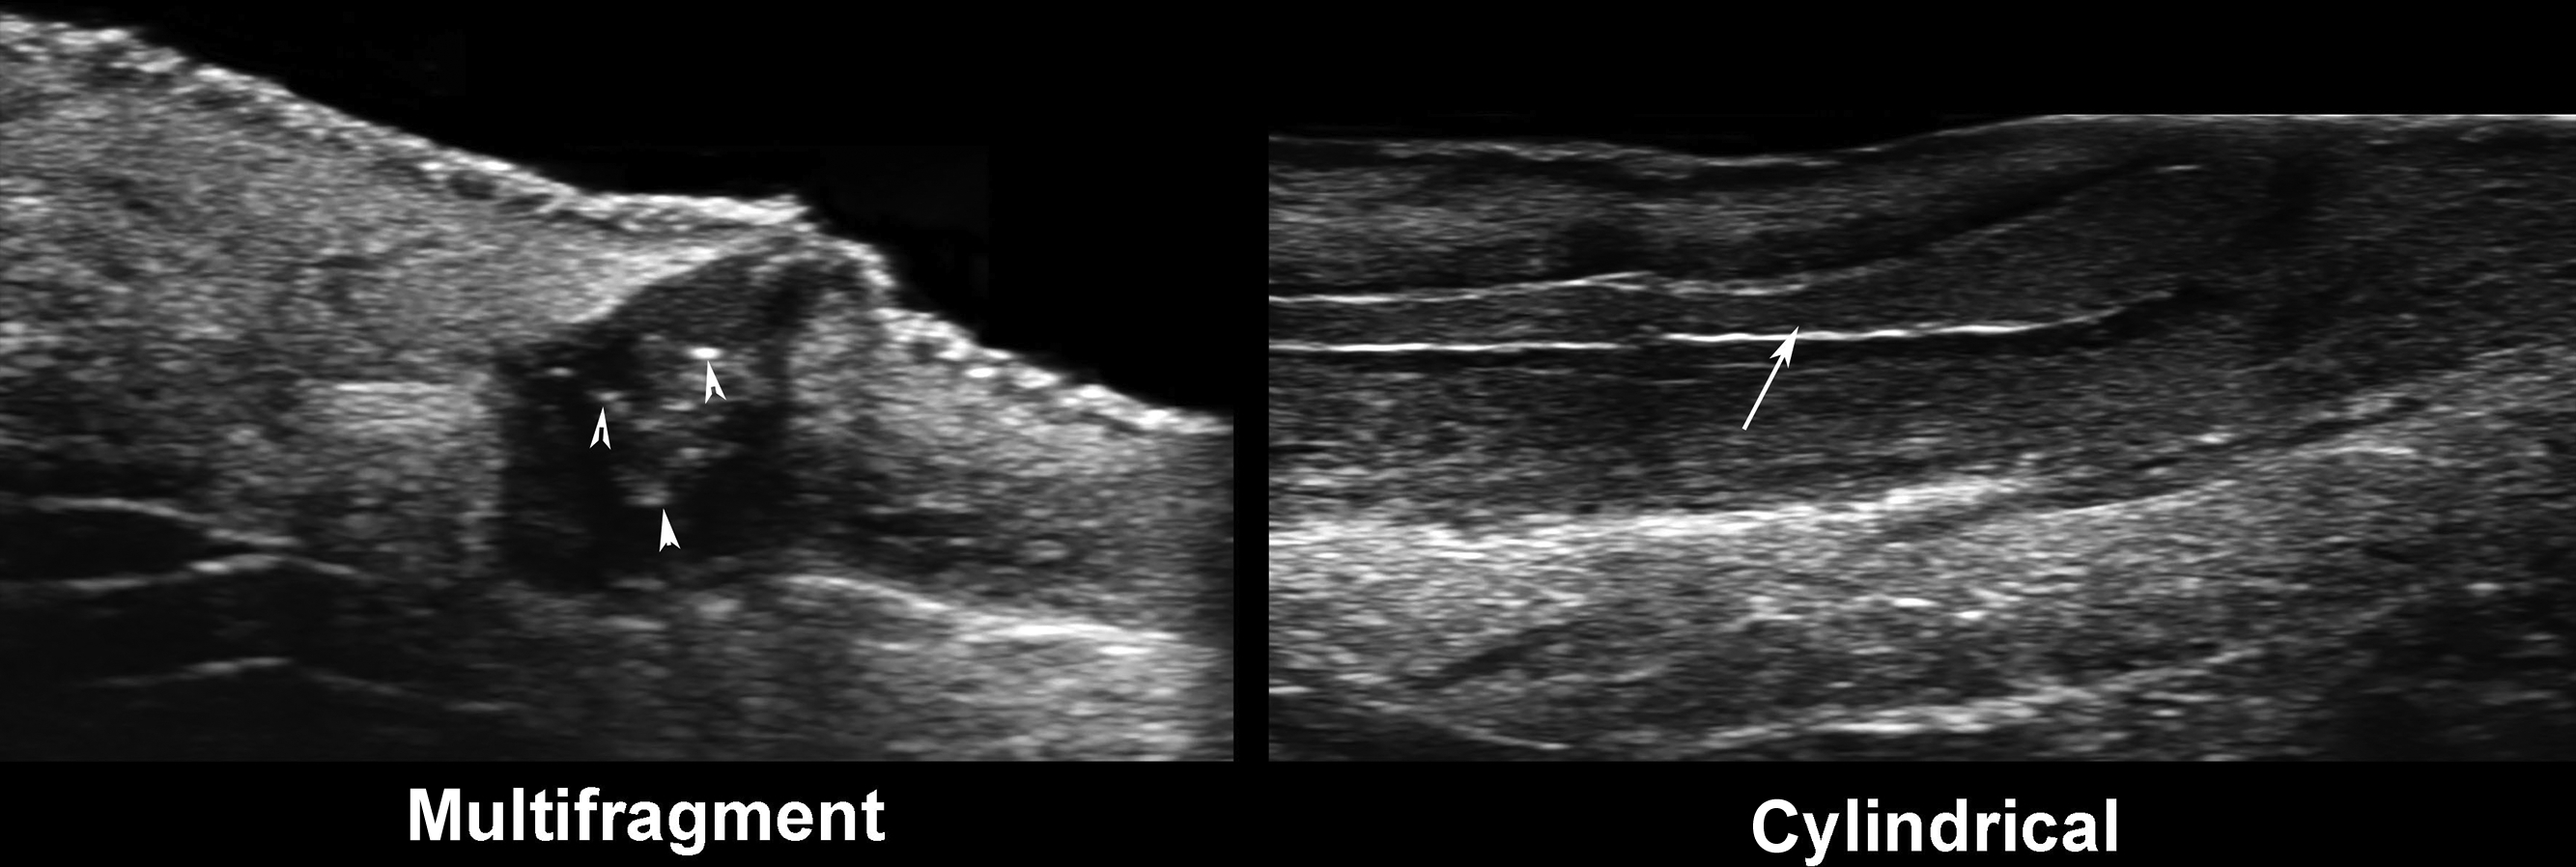

- 7.

Two types of fragmentations of the keratin are multifragment and cylindrical. Multifragment is the presence of multiple small fragments of hyperechoic linear fragments within the dilated hair follicles, fluid collections, or tunnels. The cylindrical type is composed of hypoechoic thick bands within the same structures that sometimes may show hyperechoic borders.

The signs significantly associated with the disease’s severity are the presence of “bridge” and “sword” signs and the cylindrical type of keratin fragmentation. Thus, tunnels and fibrotic changes are more frequent in these cases. The rest of the ultrasonographic signs may explain the initial formation of the primary clinical lesions.